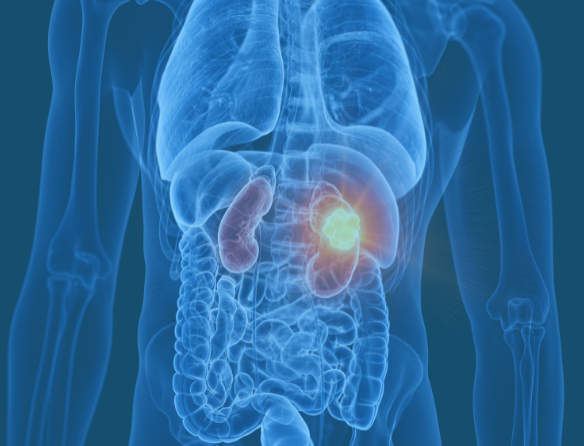

Kidney Cancer Evaluation and Treatment

Kidney cancers are often found incidentally on scans, or may present with blood in the urine or pain. We provide full diagnostic and treatment counselling, from monitoring small tumours to surgical removal, including minimally invasive options like robotic partial nephrectomy. All treatments are carried out within the NHS due to the specialised facilities required.